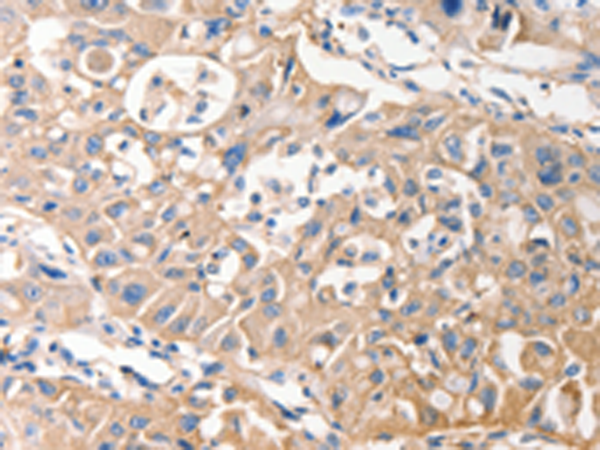

分类: 科研抗体货号: P07408别名: hK1; KLKR; Klk6应用: IHC反应种属: Human